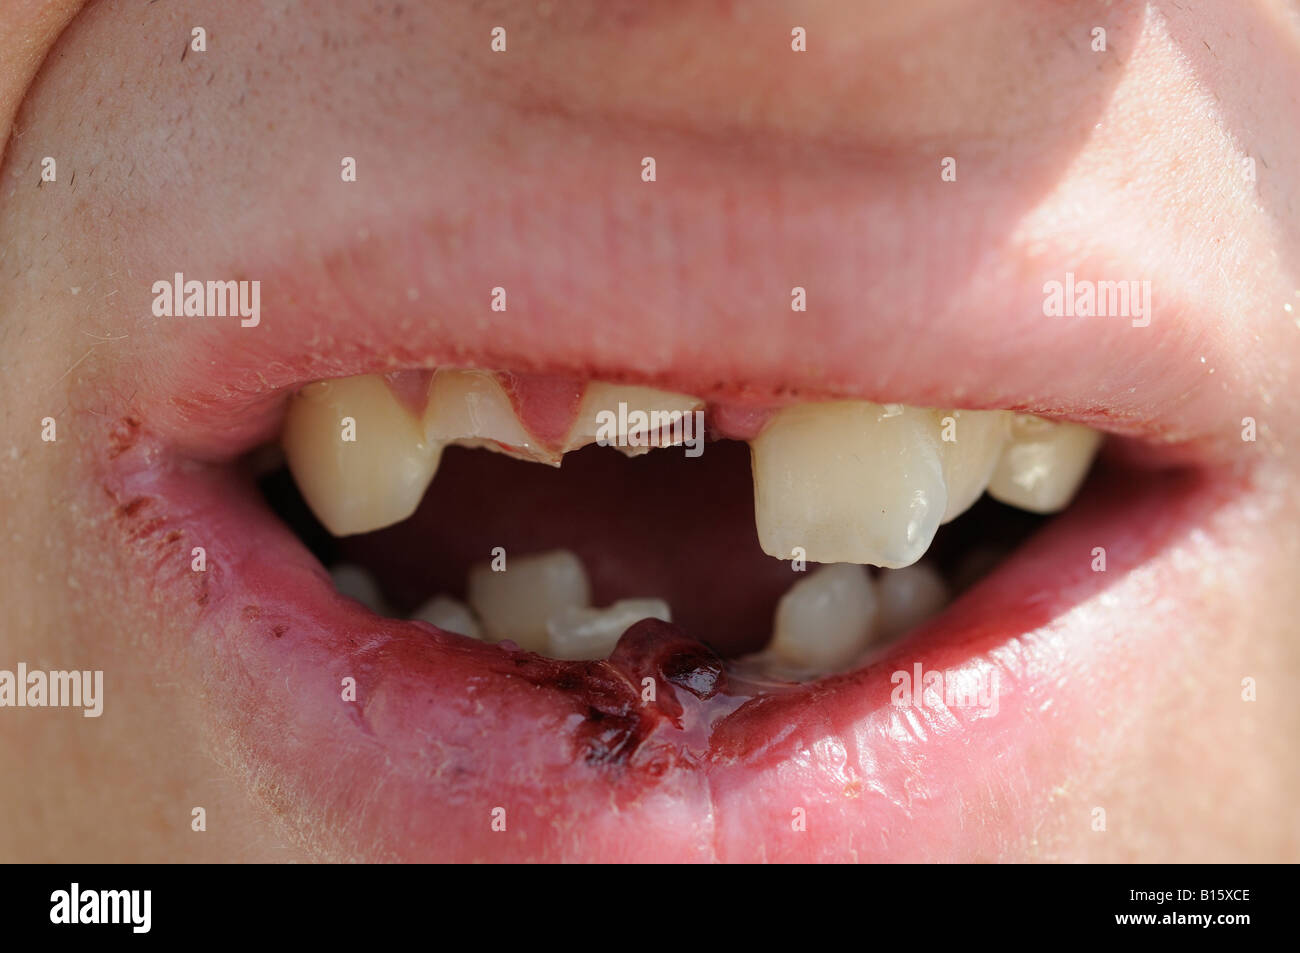

Broken Tooth Stock Photo - Alamy

www.alamy.combroken teeth lip split alamy stock after little attacked bar being

www.alamy.combroken teeth lip split alamy stock after little attacked bar being